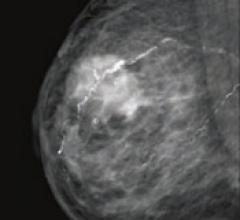

June 28, 2011 — Sectra and Philips Healthcare have signed an agreement under which Philips will acquire Sectra’s mammography modality operations for approximately $80 million. Through this deal Sectra’s Medical Systems business will focus on medical imaging information technology (IT).